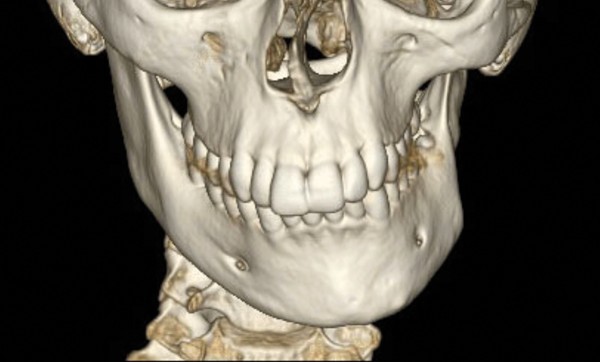

Analyse squelettique : les documents montrent une classe II squelettique modérée par rétrognathie mandibulaire dans un contexte de normodivergence. Les examens complémentaires confirment que la latérognathie mandibulaire gauche est la conséquence d’un hypo-développement des structures maxillaires et mandibulaires de ce même côté (fig. 2a, b et c). On observe sur les reconstructions 3D (à partir des coupes scanner) à l’aide du logiciel Osirix® : un corps mandibulaire fin, un ramus peu développé, un col du condyle grêle.